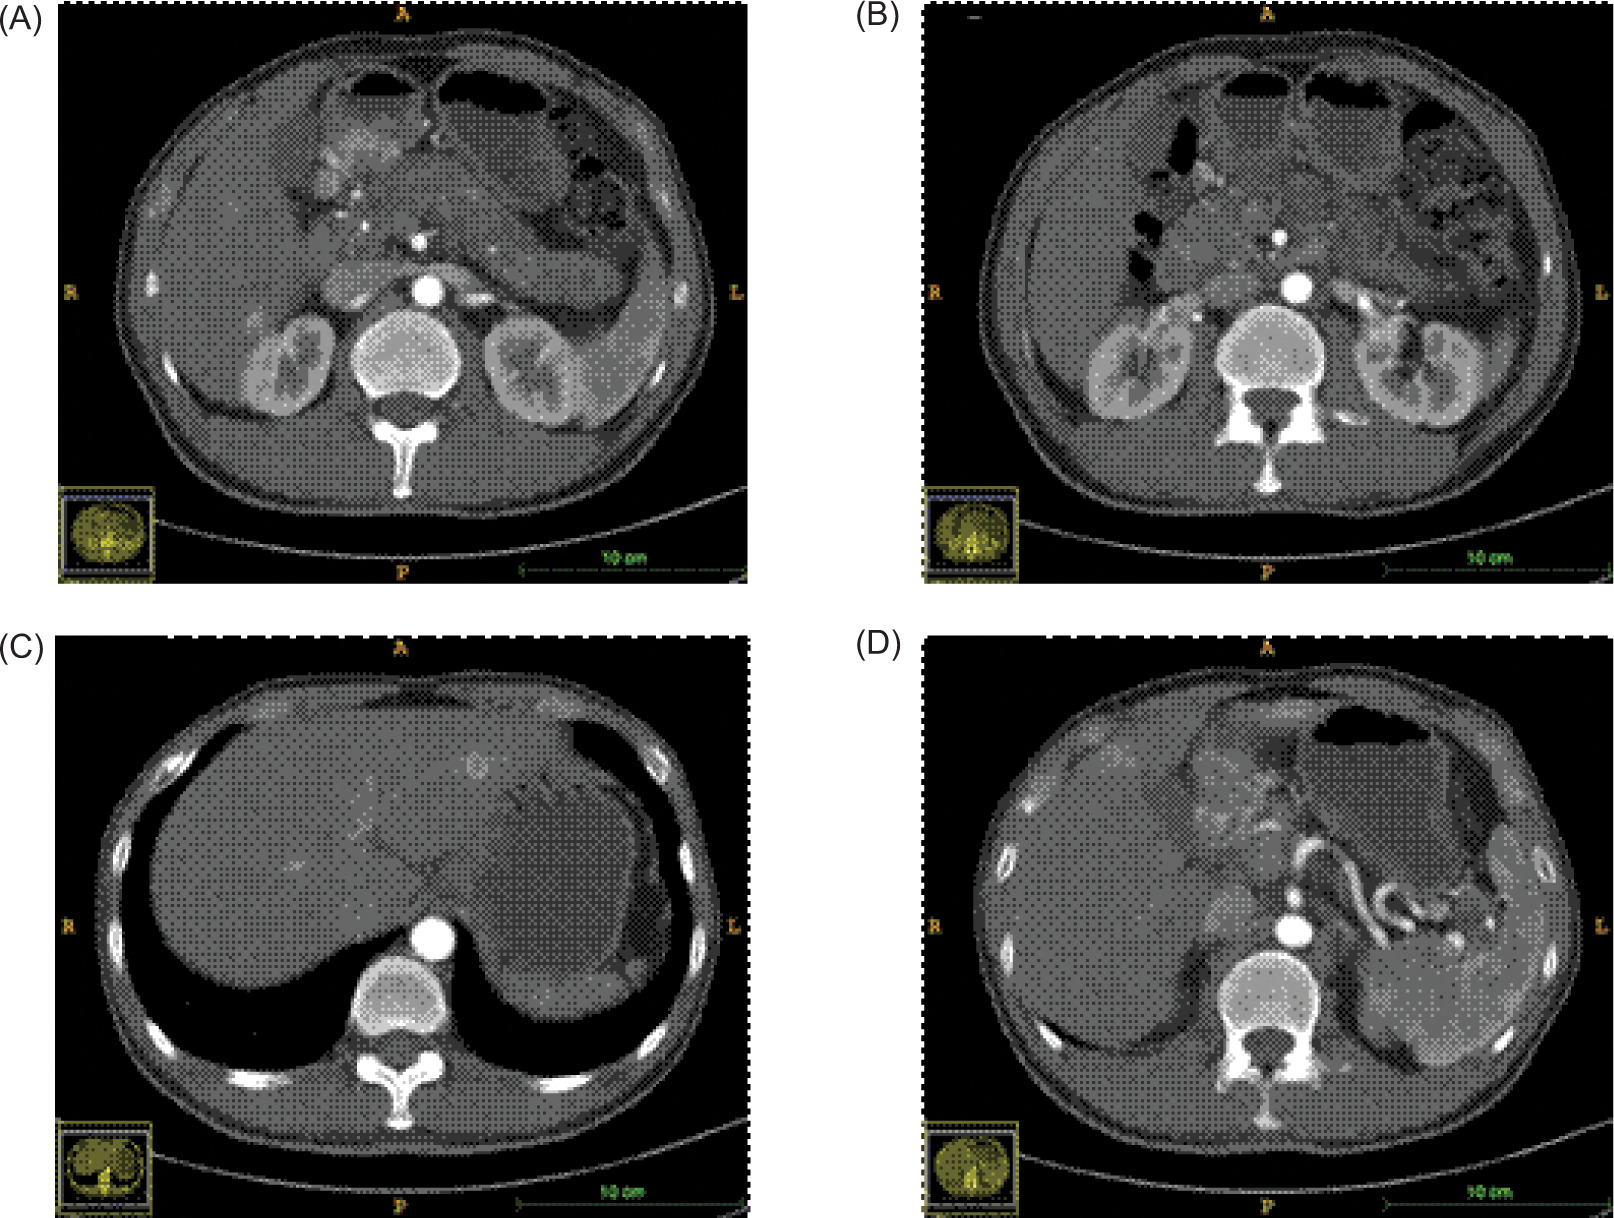

The patient demonstrated nonadherence to the regular follow-up appointments recommended by the healthcare provider. In July 2018, the patient reported experiencing abdominal pain. A contrast computed tomography (CT) scan disclosed a tumor in the antrum of the stomach, suggesting a neuroendocrine tumor, with associated metastatic tumors identified in the liver and the right renal area (Figure 1). Additionally, the CT scan revealed the presence of polycystic pancreas and polycystic kidneys. The patient underwent a gastroscopic biopsy of the gastric lesion, and immunohistochemical tests yielded positive results for Syn, CgA, and CD56, confirming the tumor as a neuroendocrine tumor. Furthermore, hyaline changes were observed in the tumor tissue (Figure 2). A subsequent 68Ga octreotide positron emission tomography (PET)-CT scan confirmed high metabolic activity in the tumors of the gastric antrum and liver, but not in the right renal area. Considering the patient’s previous diagnosis of cerebellar hemangioblastoma and these imaging findings, the probability of VHL disease was regarded as high. Genetic analysis using peripheral blood DNA identified a germline mutation in the VHL gene (c.351 G>T; p.Trp117Cys) and the POLE gene (c.C122T; p.Thr41Met). Genetic testing of the patient’s offspring revealed that his son carried the same mutations, while his sister did not display these mutations.

Figure 1: CT scanning during the first diagnosis (arterial phase). (A) lesion in the gastric antrum; (B) lesion in the left renal hilus; (C, D) lesions in the liver.